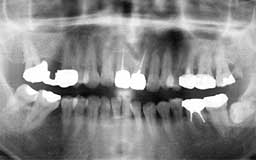

★ S君 16歳

最後に登場していただくS君は初診時16歳。すでに抜髄された歯が1本あり、他にも多数

の虫歯がありました。先に来院されていたお姉さんの話を聞いて来られた様子で、主訴はい

きなりメインテナンス希望というものでした。初診時に虫歯の治療を行い、途中親知らずを

抜歯していますが、それ以外20年間ほとんど治療をしていません。ましてや忌まわしい抜髄

や銀の被せなどとは全く無縁の世界を享受している様子です。「親知らずは早めに抜いて、

それ以外の歯は1本足りとも抜かずに済むように手入れしましょう」と夢物語のように申し

上げておりますが、実現は十分可能です。そのために必要なことが何であるかは十分わかっ

ていただけたと思います。

16歳からのメインテナンスは当時としては珍しい症例ですが、S君をそうさせた原動力は

まさに家族の愛とでもいえるかもしれません。多少皮肉な結果になっているのですが、私に

とって実に愛すべき症例ですので、ご家族にも登場していただきます。

| S君 初診時 16歳 男性 (弟) すでに1本の歯が抜髄されており、それ以外にも多数虫歯治療の形跡が認められます |

S君 20年後 36歳 初期の治療後約20年間、毎月の歯石除去と検診を継続した結果、新たに歯の神経をとること なく良好な環境を保持しています |